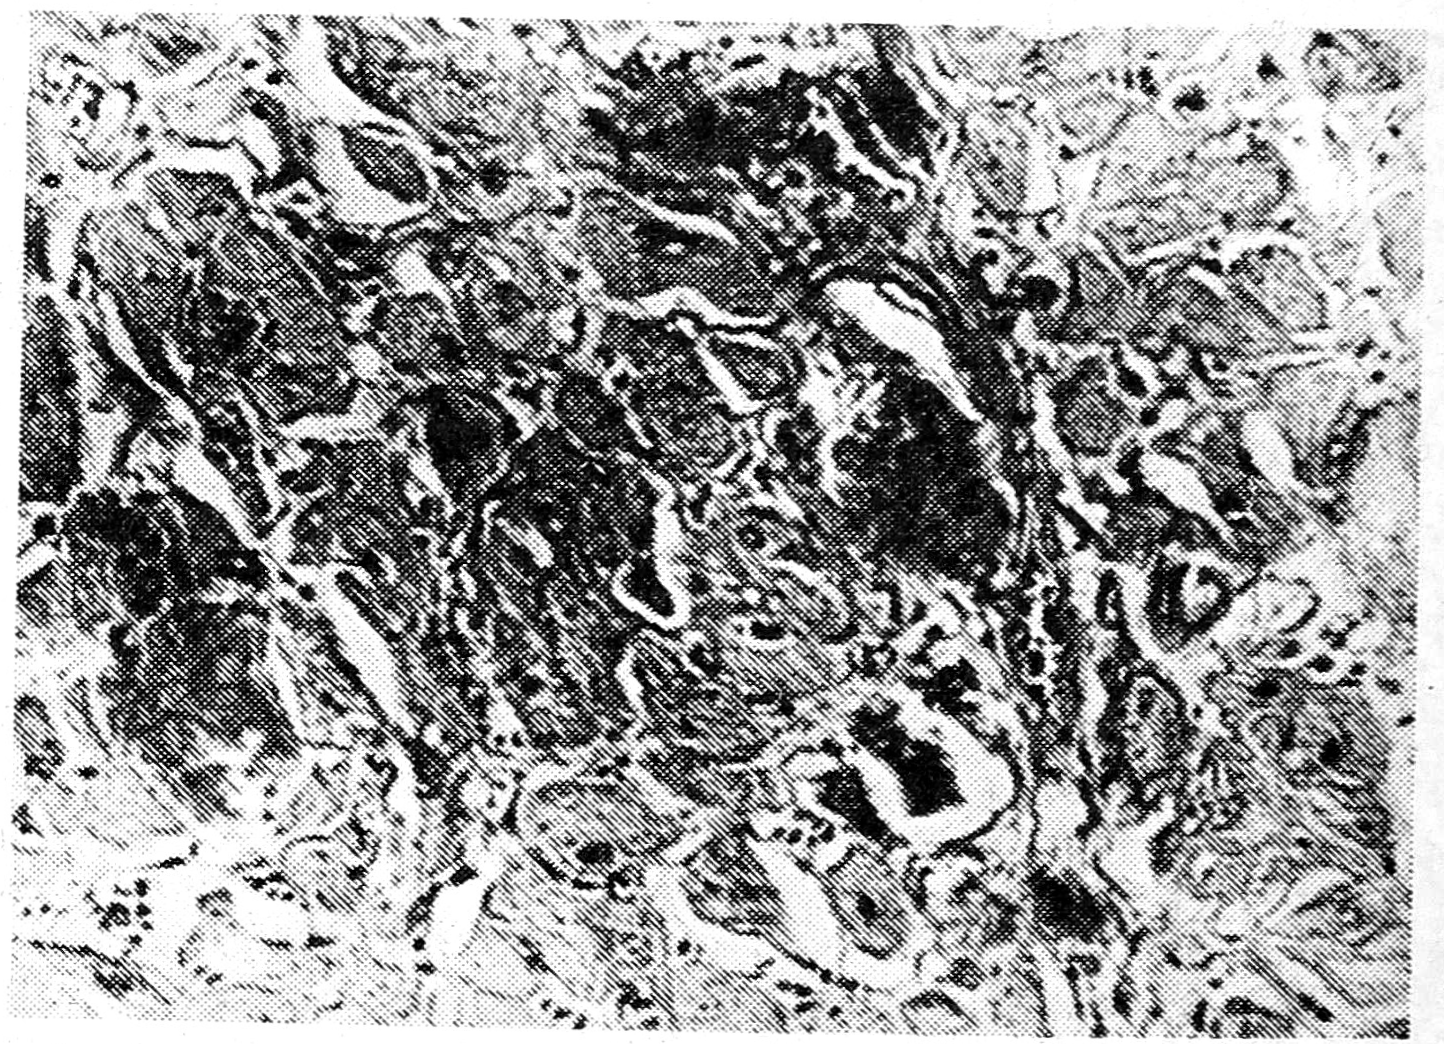

Рис. 1. Отложение амилоида в миокарде. Окраска конго красным X 600.

Проведена биопсия слизистой прямой кишки, при гистологическом исследовании обнаружено отложение амилоида в стенке сосудов.

Больной был выписан на амбулаторное лечение, однако через 2 мес вновь поступил в клинику в крайне тяжелом состоянии и умер при нарастании сердечно-сосудистой недостаточности. На секции был обнаружен генерализованный амилоидоз. На рисунке приведена гистологическая картина отложения амилоида в мышце сердца.